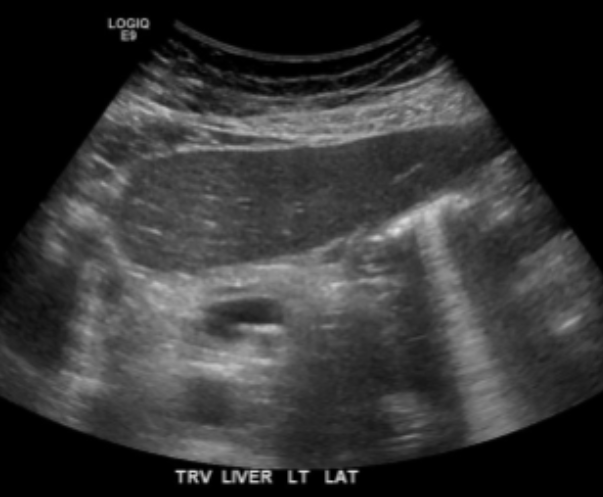

Enhancement

Caused by a structure of low attenuation adjacent to a structure of normal attenuation

Appears as a band of increased echogenicity behind an area of low attenuation

Can be diagnostically useful to distinguish fluid-filled from solid objects

Fluid filled objects have this artifact

Solid objects DO NOT have this artifact